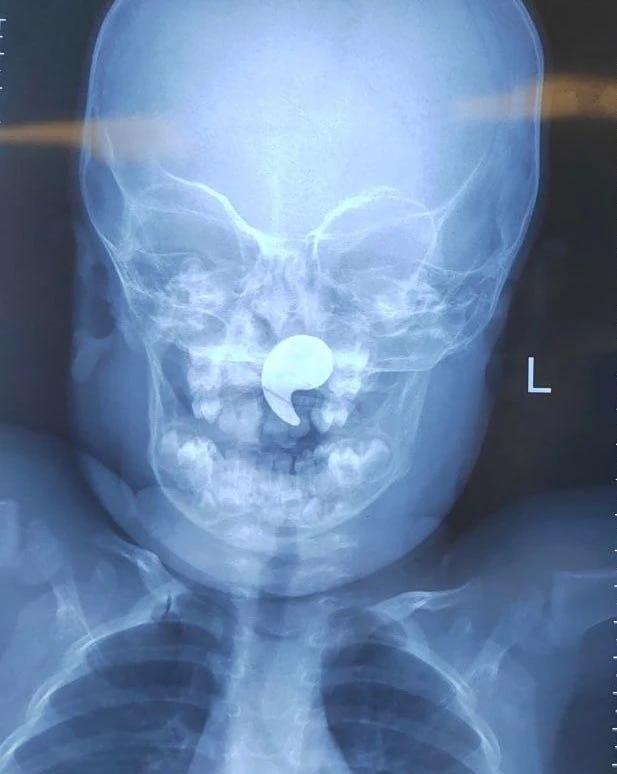

В областную больницу №1 обратились родители пострадавшей. Они рассказали, что девочка играла магнитом в форме запятой, а затем начала давиться. После попытки матери извлечь его пальцем, он сместился в носоглотку. У ребенка появились боль в горле, отказ от еды и слюнотечение.

После рентгенологического подтверждения наличия инородного тела, девочка была госпитализирована в оториноларингологическое отделение. Под общей анестезией и эндоскопическим контролем был успешно извлечен магнит. На следующие сутки ребенок был выписан домой под наблюдение педиатра.